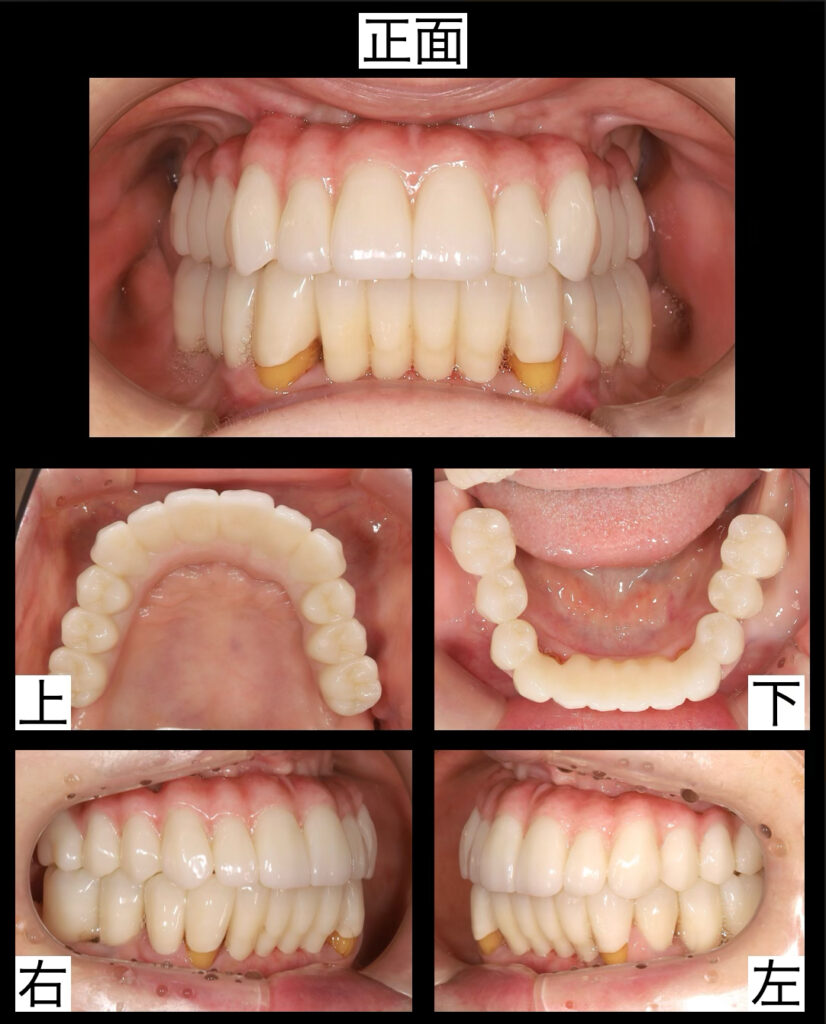

最終セラミックのセット〜笑顔を戻った瞬間〜

いよいよ、最終的なセラミック補綴物をセットする日を迎えました。

仮歯の段階でも、患者様は「これでもう十分満足です」と笑顔を見せてくださっていましたが、最終的なセラミックが口の中に入った瞬間――その表情は、まるで新しい人生が始まったかのように輝きました。色味はより自然で、透明感のある光を放ち、唇からのぞく歯のラインはとても美しく、まさに“理想のスマイル”そのものでした。(以下の写真参照)

下顎の再構築『残せる4本の歯を最大限に活かす』

精密な診査・診断の結果、下顎で保存できる歯はわずか4本でした。残せたのは、左右の犬歯(けんし)と第1小臼歯(だいいちしょうきゅうし)です。

これらの歯は、下顎の中でも噛み合わせや見た目のバランスをとるうえでとても重要な歯です。私たちは、この4本を土台として前歯部の再構築を行い、奥歯の部分にはインプラント治療を計画しました。

前歯と奥歯の連携で「噛める」と「美しい」を両立

奥歯のインプラントがしっかりと噛む力を支え、前歯は残っている天然の歯を利用してセラミックで美しく修復しました。結果、見た目にも自然で、機能的にも安定した『理想的な咬合(こうごう)』を実現。

患者様も「しっかり噛めるようになった」「自然に笑えるようになった」と喜ばれていました。